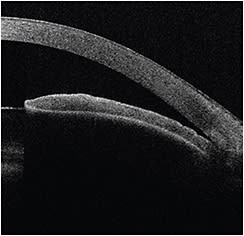

UBM can be used to image the ciliary body, its relationship to the iris and its effect on the iridocorneal angle. It is particularly useful for determining if the anatomical characteristics of plateau iris syndrome are present, such as anterior displacement of the ciliary body (Figure 2). Additionally, it is useful for the detection of ciliary body effusions associated with secondary nonpupillary block-angle closure, for example, in the idiosyncratic reaction that may occur in patients on topiramate (Topamax, Janssen Pharmaceuticals).

UBM of the anterior chamber angle (Figure 2) discloses a closed angle and an anteriorly situated ciliary body, characteristic of plateau iris syndrome.